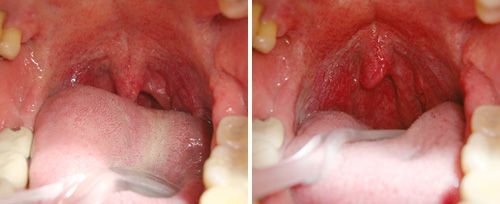

Nightlase is a ground-breaking laser for treatment of snoring. Unlike other surgical treatments, there is no cutting or removal of any oral tissue. Our laser therapy utilizes non-invasive light wavelength to gently stimulate the tightening effect by generate the collagen production and elevates the soft palate. This therapy strengthens patient’s inner oral tissues to increase the airway and reduce the intensity of snoring. Treatment requires no needles, no anesthesia and no chemicals.

This non-surgical therapy is a fast, non-invasive technique for the treatment of snoring. Because the laser therapy utilizes gentle light wavelength, it is virtually painless and there is no need for anesthesia or numb during and after the procedure. This airway-tightening technique is considered safe and the most convenient because patients don’t have to wear any appliances or suffer any surgery.